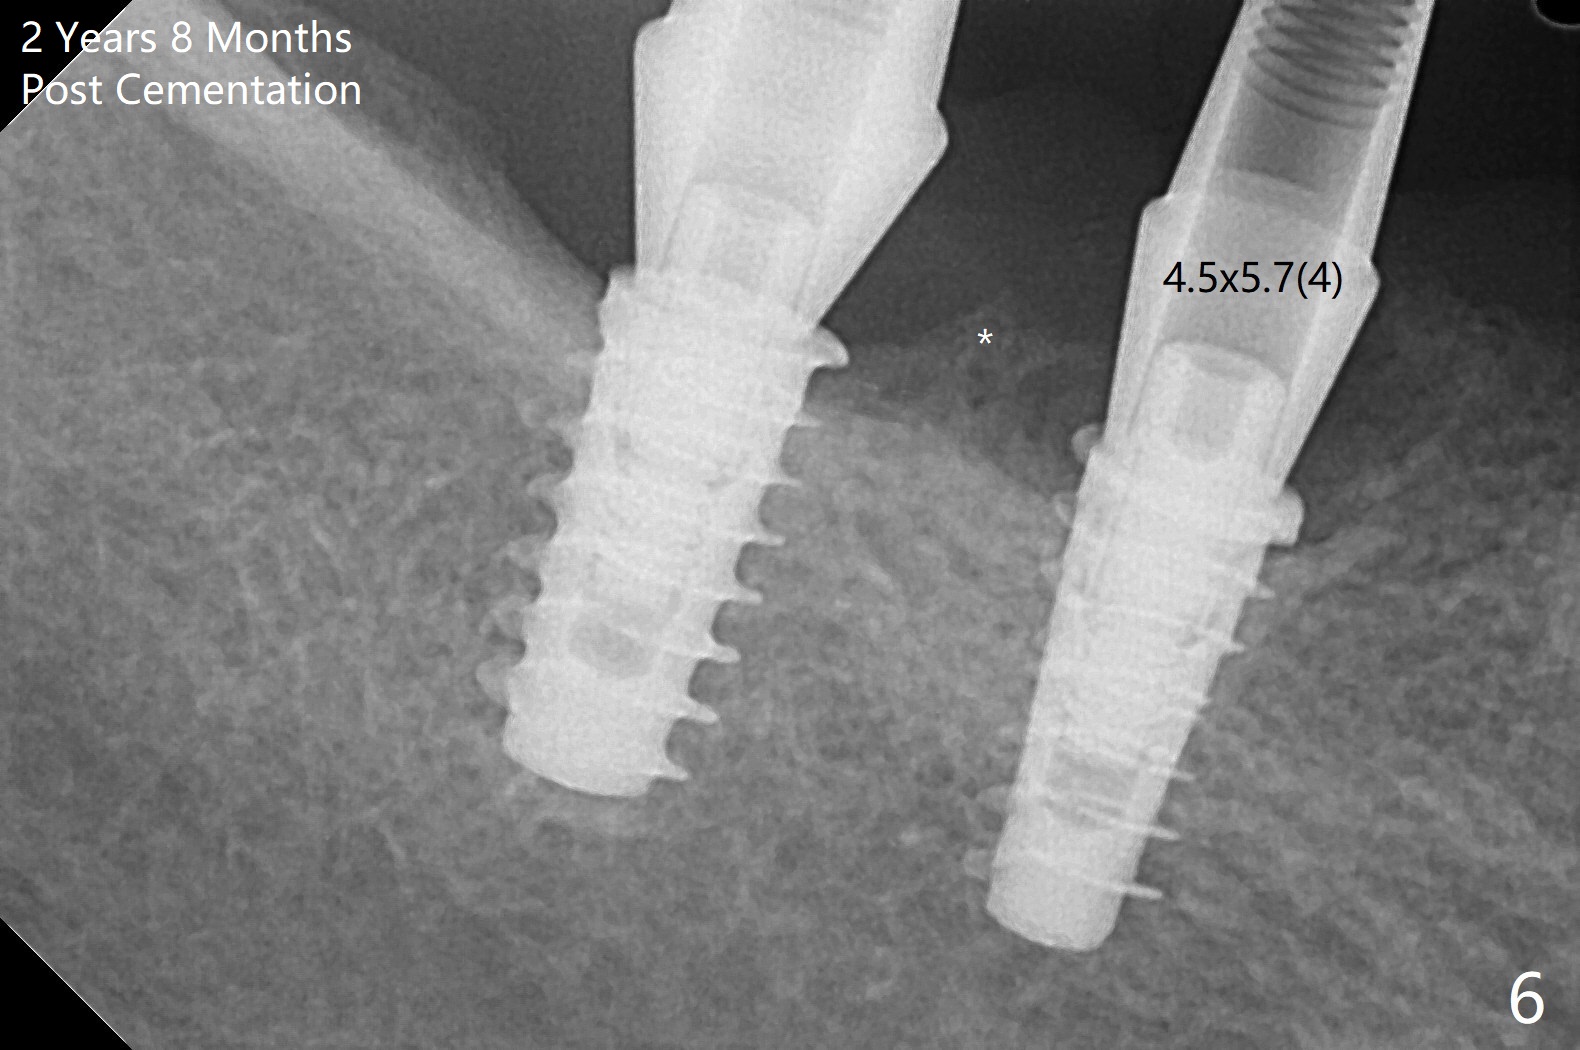

Following osteotomy, 4.5x11 and 5x9 mm dummy implants are placed at the sites of #30 and 31, respectively (Fig.1).  Due to limited inventory of Magicore and patient's in-cooperation, FC implants (4.5x9 and 5x9 mm) are placed (Fig.2).  A healing abutment (6x4 mm) is placed at #31 because of low torque (overprep), while a pair abutment (6.5x5.7(4) mm) is placed at #30.  Vera Graft is placed with autogenous bone (*).  The implant/abutment ratio at #30 is unfavorable.  If the implant turns out to be loose, immediate implant should be larger in the future.  Note bone growth, especially at #30, 2.5 and 4 months postop (Fig.3,4).  In fact the abutments are incompletely seated.  The crown of #30 is loose 2 years 8 months post cementation, while the abutment at #31 remains incompletely seated (Fig.5).  The latter is completely reseated after separating the crown, while a smaller one is seated at #30 (Fig.6) due to use of a small healing abutment earlier (Fig.5).  A good piece of news is the presence of the bone between the implants (Fig.5,6 *), which contributes to interimplant papilla.  Return to Lower Molar Immediate Implant, Prevent Molar Periimplantitis (Protocols, Table), IBS77, 2-5 Xin Wei, DDS, PhD, MS 1st edition 09/22/2017, last revision 12/01/2020